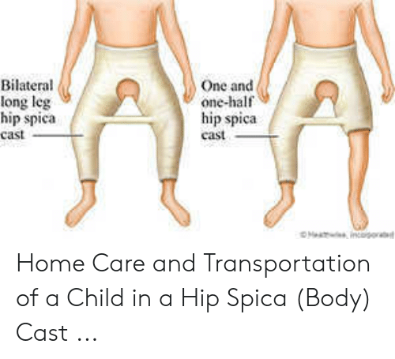

A child treated with a hip spica with hips in a reduced position